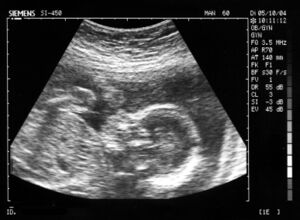

Ecografia di un feto di 23 settimane

1. ultrasuoni ad alta frequenza, da 1 MHz a 10 MHz, usati soprattutto come mezzo diagnostico in medicina;

• Gli ultrasuoni ad alta frequenza vengono usati in medicina come ad esempio nell'ecografia che permette di osservare, senza danno per il paziente, parti interne del corpo umano con una metodologia simile a quella basata sui raggi X, ma con un dettaglio di risoluzione e una penetrazione molto minori. Infatti, facendo vibrare cristalli di quarzo, si generano ultrasuoni che vengono diretti ad angolature diverse attraverso le parti da studiare. Si rilevano, molte volte ogni secondo, le onde riflesse, in modo da ottenere una serie di immagini che, rielaborate in sequenza, formano un filmato. Per ulteriori notizie si veda la pagina riflessione del suono.